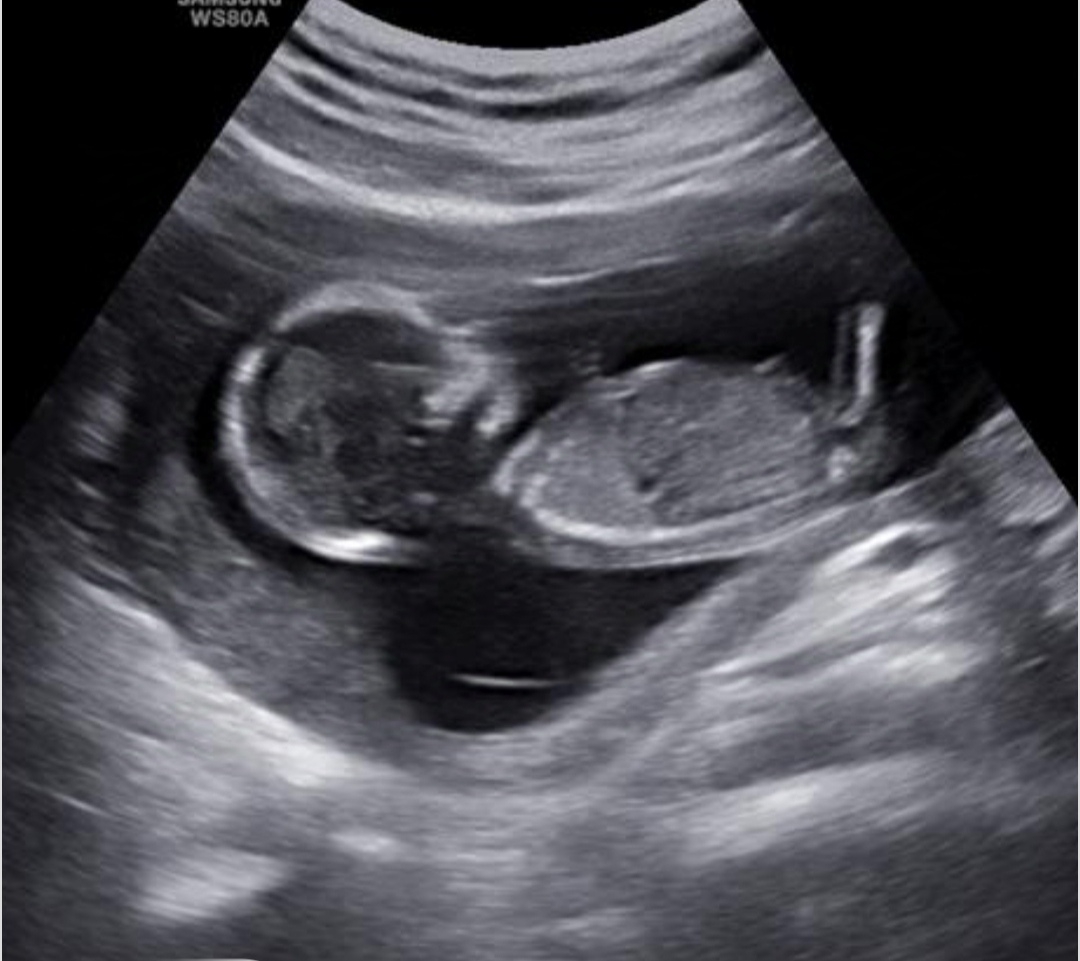

سلام خانوم دکتر آزمایش ان تی امروز تونستم جوابش بگیرم بنظرتون خوبه

سلام. نه جنسیت که معلوم نمیشه. آزمایشتم خوبه کم خطره

مبارکتان باشد ریسک محاسبه شده برای سندروم های ژنتیکی تریزومی ۲۱ و تریزومی ۱۸ و 13 همگی در محدوده کم خطر قرار داشته و منفی هستند. در حال حاضر نیاز به هیچ بررسی دیگری از جمله غربالگری مرحله دوم نیست و فقط در هفته هجده بارداری مانند تمام مادران سونوگرافی آنومالی اسکن برای ارزیابی ساختارهای بدن جنین و همچنین آزمایش Ntd screen برای ارزیابی اختلالات لوله عصبی (این بررسی ضرورت جدی انجام ندارد و فقط در صورت صلاحدید پزشکتان درخواست گردد) انجام دهید🌹🌹